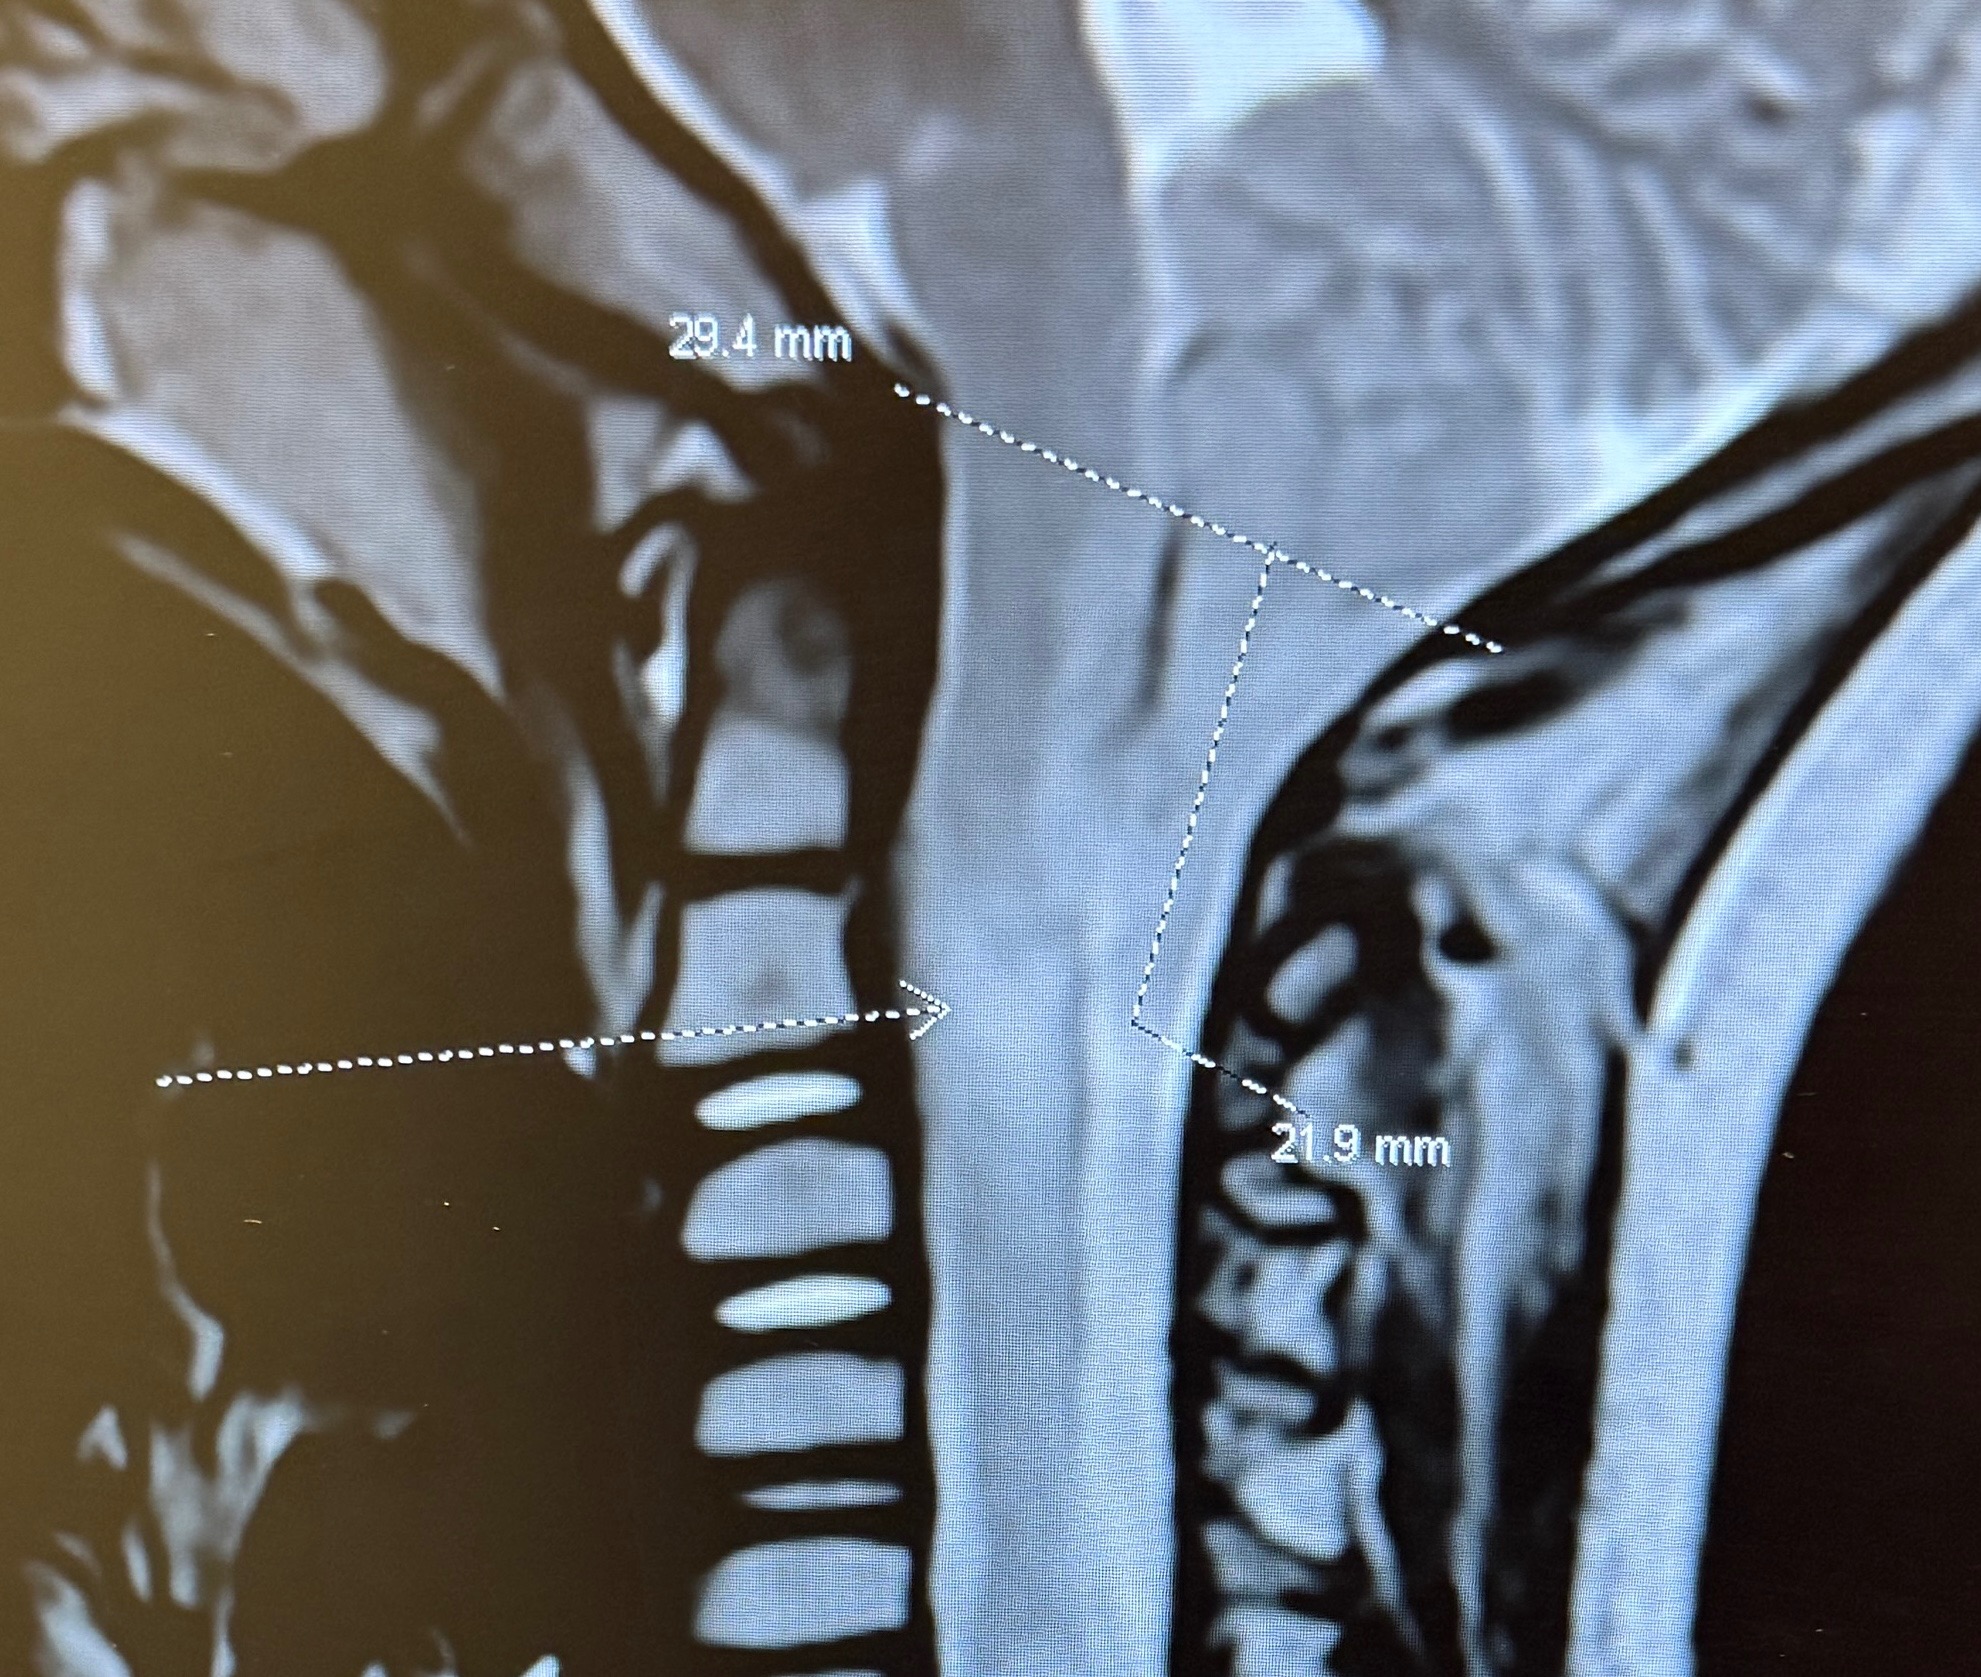

On June 24th Edgar had a MRI ordered by his eye doctor from having continuous eye pain over the last six months. What they found on the MRI was not what we were expecting at all. He was diagnosed with Arnold Chiari Malformation Type 1. We were told he had an over abundance of brain fluid, creating swelling in his brain and that we needed to follow up with a Neurosurgeon in LA.

The doctor explained how Edgar’s brain has slipped 22 mm down his spinal canal to his second vertebrae in his neck. He’s on heavy restriction till the surgery. He’ll be in ICU after surgery for a few days recovering. Once at home, he’ll be on bedrest for two weeks. He’ll sleep upright or slightly elevated for 6 weeks. He won’t be allowed to be submerged in water for 6 weeks as well. He has follow up appointments set after surgery on August 5th and September 9th both in LA.